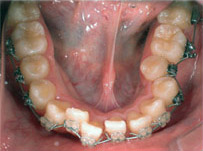

Before

Proceeding

After